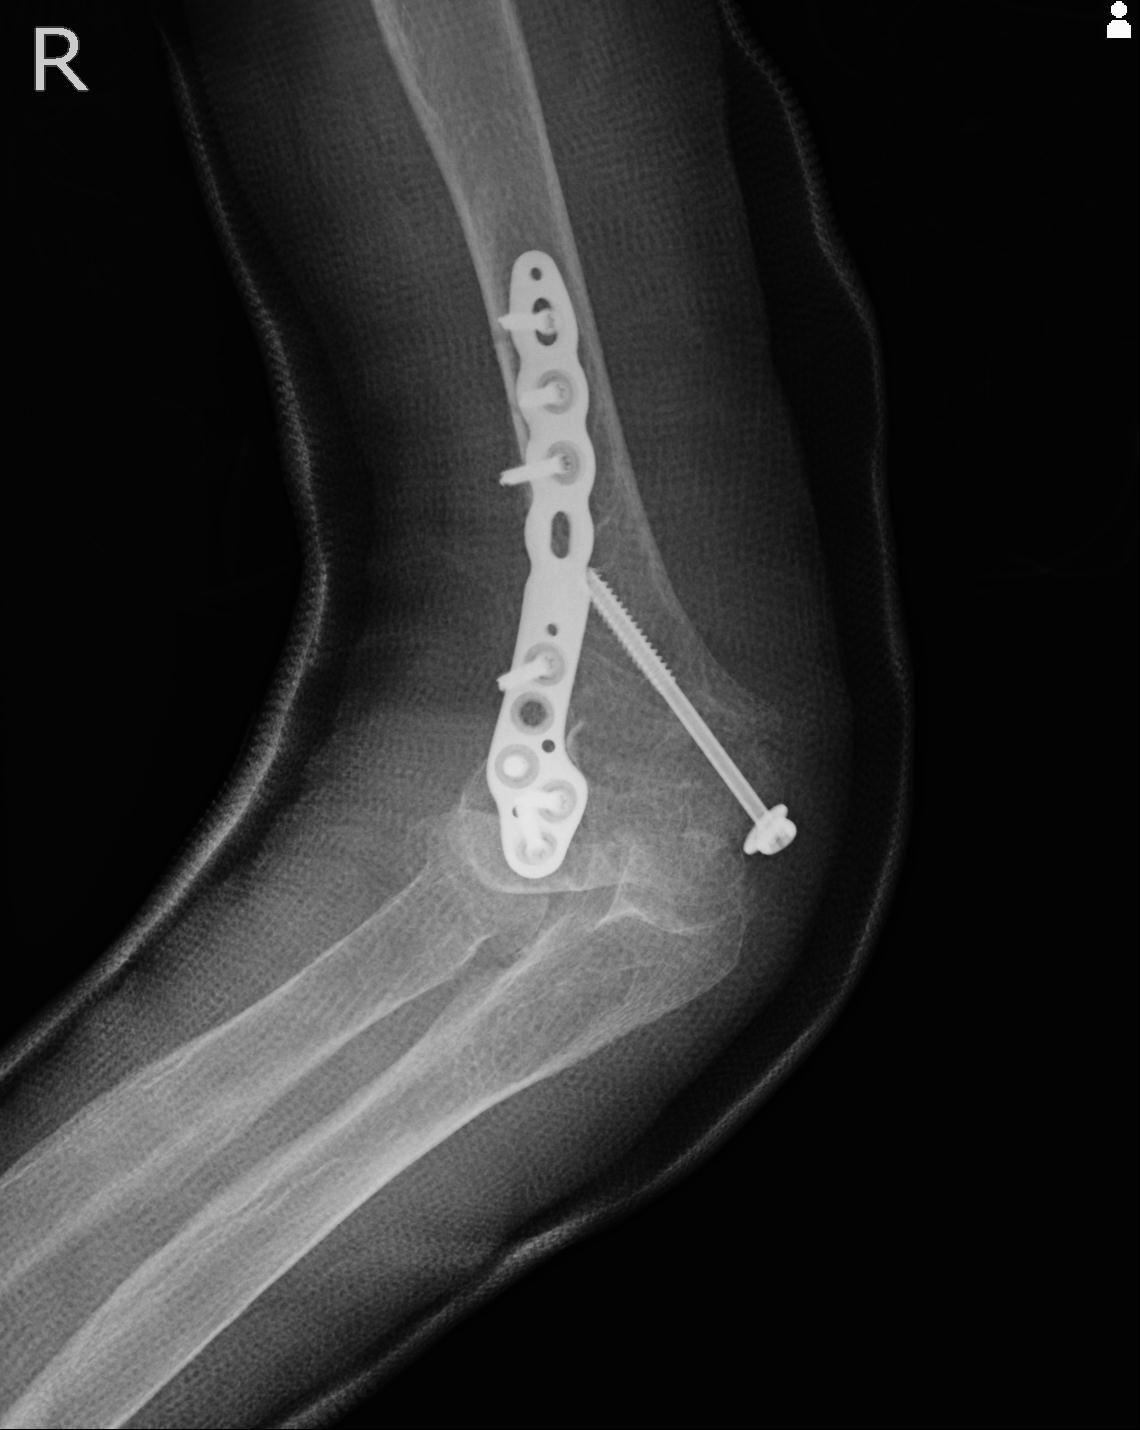

56476 8/28 4R 1/21 2R 左足関節 デジカメ写真 72歳女性 右足関節AS

102755 1/4 2R 1/15 2R 右足関節 68歳女性 右三果脱臼骨折